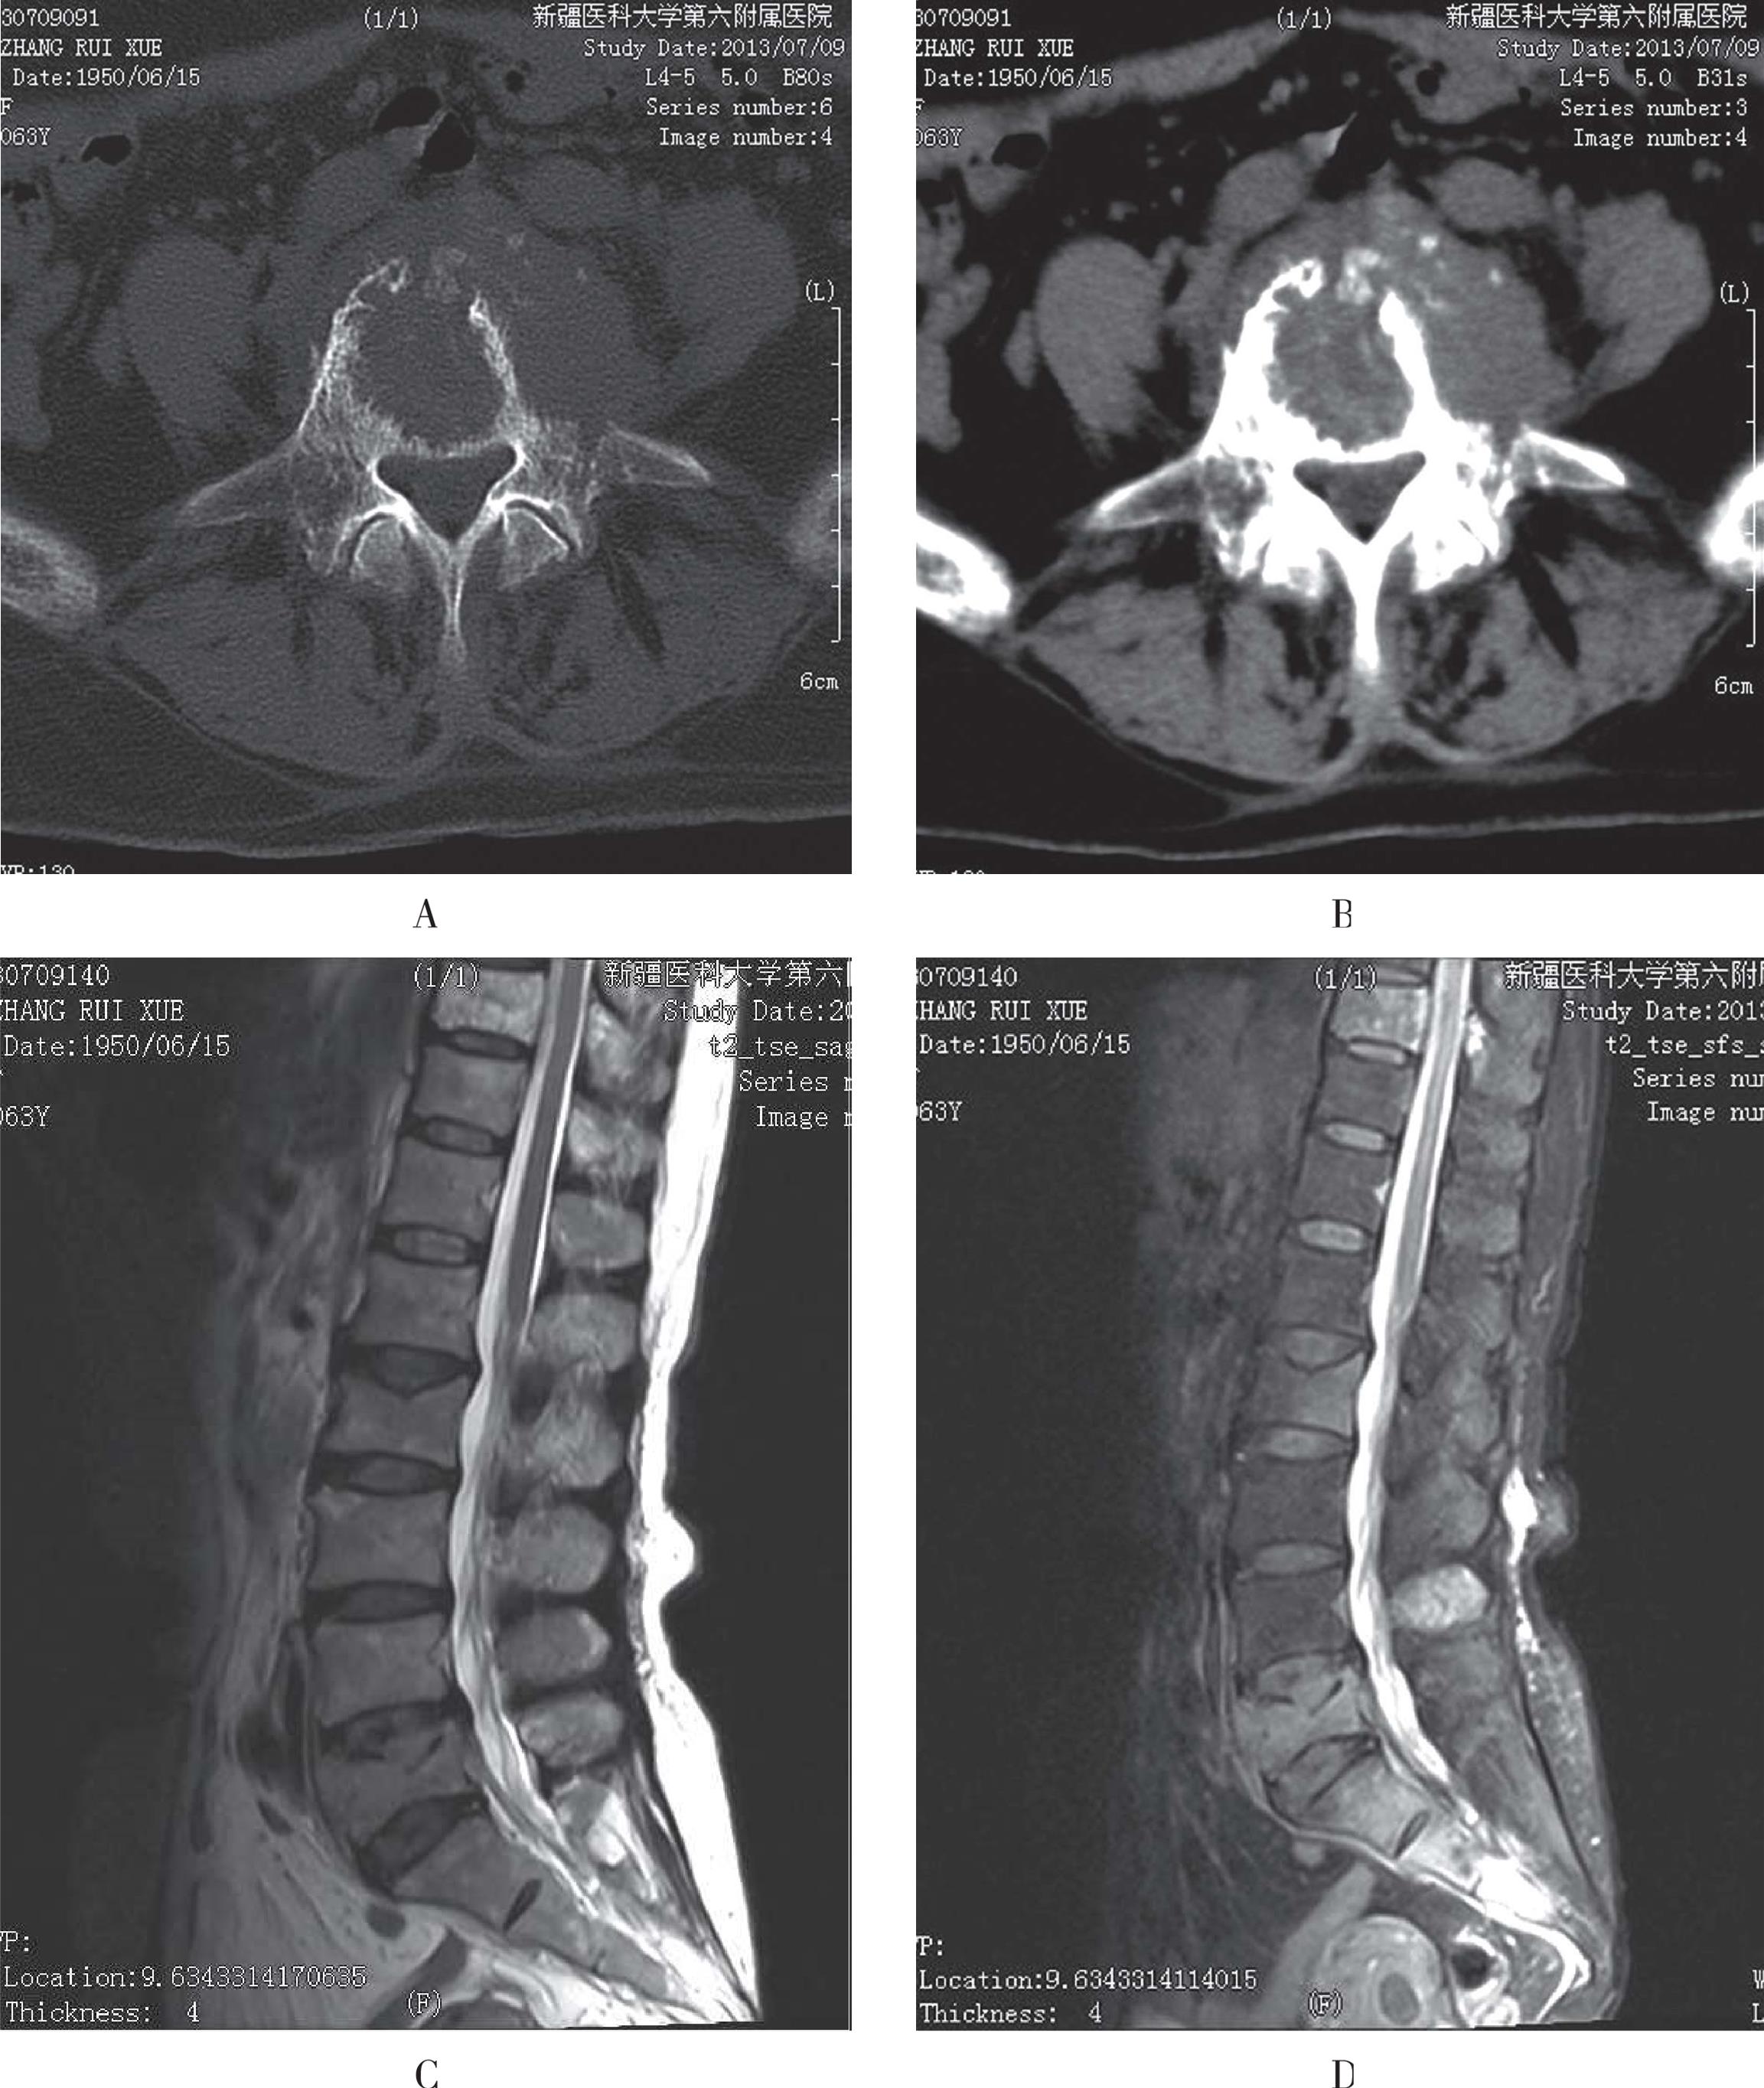

CT常常显示大量、多发、巨大的骨内破坏灶,破坏灶内骨小梁消失,甚至骨皮质破坏;骨髓瘤造成的骨破坏以髓内松质骨为主,骨皮质破坏出现较晚。一些X线片仅表现为骨质疏松,CT可显示细微的骨质破坏,在出现脊柱压缩性骨折时,CT可显示椎管内脊髓及神经根有无受压以及椎体周围有无软组织肿块等。CT检查的优点有:①能证实X线检查结果;②能更好地确定病变范围,尤其是髓外浸润病灶的范围;③能发现X线检查阴性的多发性骨髓瘤病灶,尤其是病变早期(图3-52A、图3-52B)。

MRI是检测骨髓瘤最敏感的影像学检查方法,它可在骨质破坏之前显示骨髓内病灶的浸润,以T1WI和STIR显示较好,MR检查的价值还在于检出非分泌型的骨髓瘤,在穿刺出现假阴性结果时指导穿刺部位,并可判断椎体压缩的危险性以及有无脊髓、神经根的压迫。骨髓内仅5%~20%异型浆细胞浸润时,脊髓的MRI信号正常,骨髓内大量肿瘤细胞浸润时,正常骨髓组织被广泛代替,脊髓呈现为T1WI弥漫性均匀低信号,T2WI信号增高;肿瘤细胞聚集成瘤结节时骨髓在T1WI表现为斑片状或结节状低信号,T2WI信号增高,病灶具有多发性,多不对称,骨髓瘤还可表现为“盐-胡椒状”,为肿瘤出现弥漫性浸润同时伴有局部瘤细胞聚集成团,在脂肪抑制T2WI显示最为明显。增强后骨髓瘤病灶呈弥漫性、不均匀片状、结节状强化(图3-52C至图3-52E)。

A、B. CT示骨盆诸骨广泛、较大骨质破坏区,其内未见骨小梁,临近骨皮质变薄;C. T1WI双层股骨头、颈及髋臼见多发斑片状、结节状低信号,局部骨皮质欠连续;D、E. T2WI双侧股骨头、颈及髋臼、耻骨内多发病灶信号增高,T2-tirm上病变呈高信号

图3-52 骨髓瘤的影像学表现